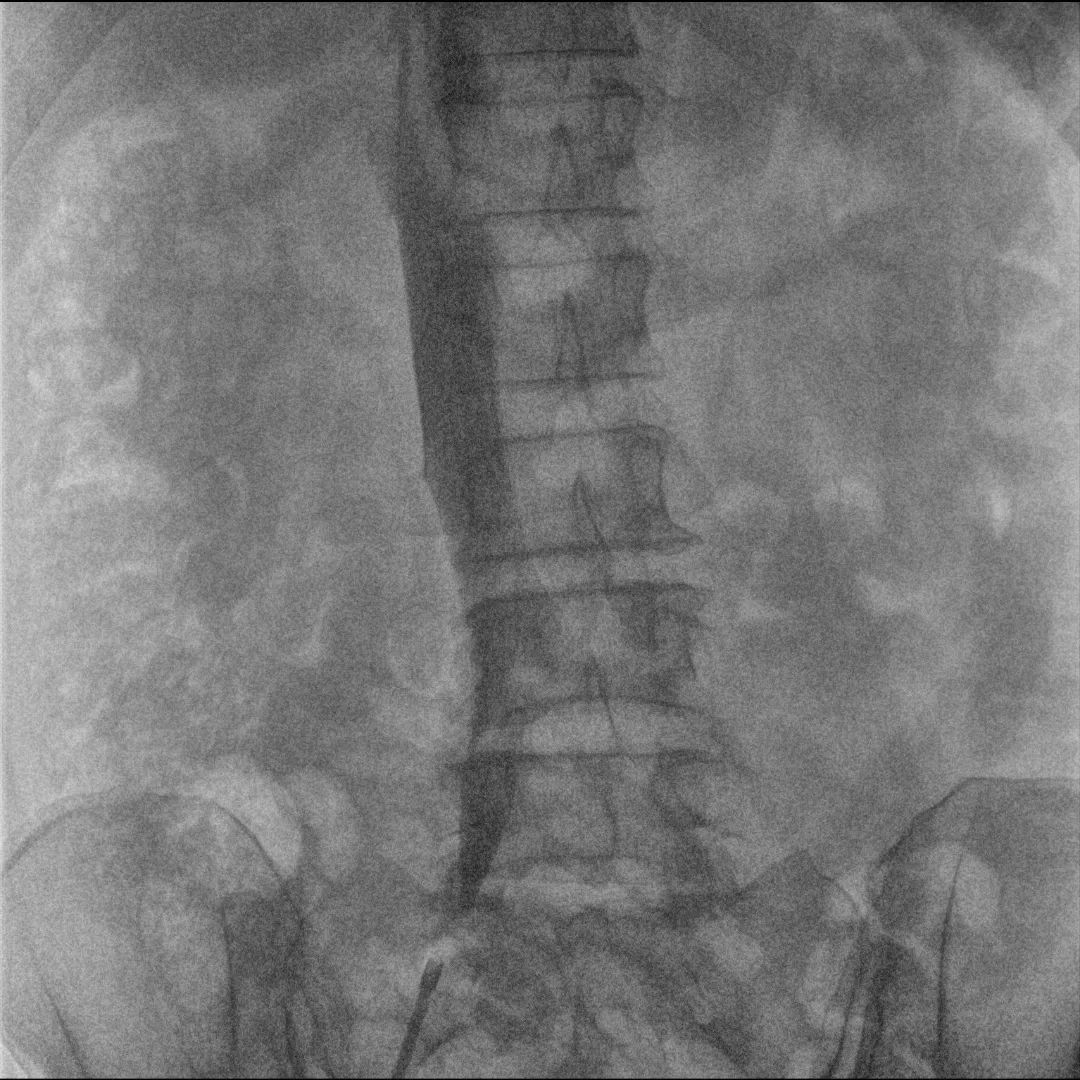

After completing thorough preoperative preparations, including complete blood count tests, kidney function assessments, and coagulation tests to exclude any surgical contraindications, the hospital’s interventional team proceeded with the surgery. Under the real-time imaging guidance of Perlove Medical’s mobile flat-panel interventional C-arm PLX7100A, the physician inserted the filter via the femoral vein into the inferior vena cava, effectively “catching” the lethal emboli flowing toward the heart and lungs. Additionally, a thrombolytic catheter was successfully implanted in the popliteal vein.

Perlove Medical’s Mobile Flat-Panel Interventional C-Arm Intraoperative Imaging

Perlove Medical’s mobile interventional C-arm PLX7100A provides high-resolution, real-time intraoperative images, allowing the physician to clearly observe the vascular structures and thrombus locations, ensuring more accurate filter placement.